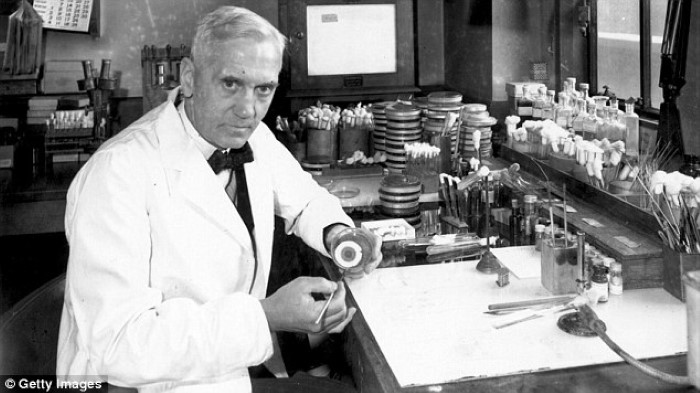

بنسلين

كان السير “ألكسندر فلمنج” يقوم بتجارب على المكورات العنقودية عام 1928، حين ترك وبالصدفة وعاء مفتوحًا مليئًا بالبكتيريا، فتشكلت طبقة من العفن على الوعاء والتي دمرت جزئيًا البكتيريا. وقد استغرق الأمر 13 عامًا من الأبحاث، وفي النهاية تم تحويل هذا العفن والفطريات إلى البنسلين، وكانت بداية المضادات الحيوية.